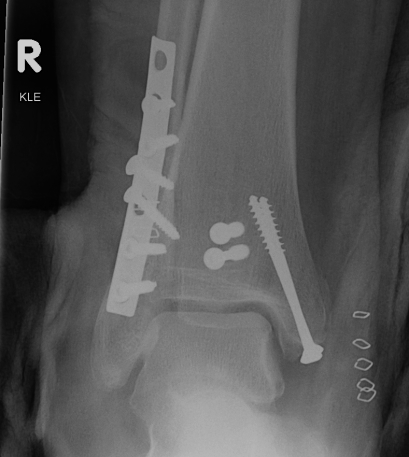

Buttress plate / Antiglide Plate

- physically protect underlying thin cortex

- often used with metaphyseal fixation

- buttress is intra-articular (tibial plateau)

- antiglide is metaphyseal - diaphyseal

1. Neutralisation plate

Neutralisation plate

- used to protect lag screws

- conduct part or all of the force from one fragment to another

- protect the fracture fixation from bending, shear, and rotation

- e.g. lateral malleolus fractures - lag then apply a derotation plate